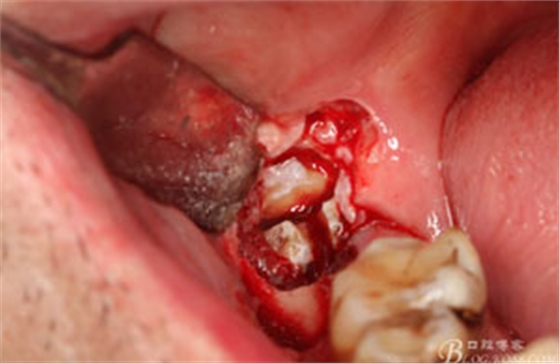

圖9.高速牙鉆分牙:

圖10.先頰舌向橫斷、然后再把牙冠近遠(yuǎn)中向縱分

圖11. “T”型的分牙。